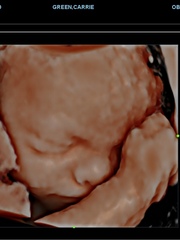

We've been for a 4d scan today. It was really lovely - heard the heartbeat for the first time and got really emotional. Baby insisted on having their hand in front of their face (again!) so the sonographer gave them some gentle encouragement to move and we now have some pictures of their little face!

@yfenniChristie oooo it's amazing seeing your little one in 4d right my boy was the same yesterday fists up like a boxer but we actually got some nice pics of him cuddled up to his arm. My sonographer did the same. I said to DH it's a good job we knew the sex before hand as sonographer gave us a crotch shot straight away then nervously asked us if we knew the gender. We said yes and he said "yes he's still a boy" 😂x

@MissM94 bet it was still nice to see you LO's face though. I got 40 pictures and only 6 of em he has a smooth face rest look all drippy like a mud monster. I'll put up my favourite and most clear picture and one of the melty ones to show you what I mean 😂

@MissM94 you have a very beautiful baby such a cute nose. I keep looking at my pictures to becoming a but obsessed.